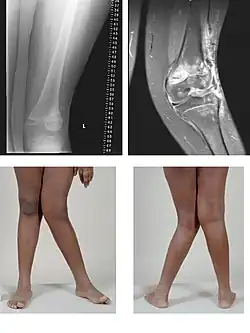

| A very severe case of genu valgum of the left knee following bone cancer treatment | |

Genu valgum, commonly called "knock-knee", is a condition in which the knees angle in and touch each other when the legs are straightened.[1] Individuals with severe valgus deformities are typically unable to touch their feet together while simultaneously straightening the legs. The term originates from Latin genu 'knee' and valgus 'bent outwards', but is also used to describe the distal portion of the knee joint which bends outwards and thus the proximal portion seems to be bent inwards.

Mild genu valgum is diagnosed when a person standing upright with the feet touching also shows the knees touching. It can be seen in children from ages 2 to 5, and is often corrected naturally as children grow. The condition may continue or worsen with age, particularly when it is the result of a disease, such as rickets.[2] Idiopathic genu valgum is a form that is either congenital or has no known cause.